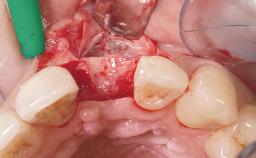

Immediate Flapless Placement of an Implant in a Maxillary Left Central Incisor Site

A 42-year-old female patient was referred to our clinic at the School of Dentistry of the University of São Paulo in November 2004, presenting a deficient restoration in the upper left central incisor. The clinical examination revealed no gingival retraction or any signs of gingival inflammation and, therefore, previous periodontal treatment was not considered. The patient presented a high lip line at full smile and a thin tissue biotype. This combination characterized a high-risk situation from an anatomic point of view, which required careful preoperative planning and cautious surgical execution.

Placement Protocol Immediate implant placement

Tooth Site Maxillary incisor or canine

Socket Integrity Sufficient, with intact bone walls

Bone Volume Sufficient, with intact walls